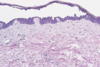

Give examples of spongiotic skin inflammation

Contact dermatitis

What is the pathophysiology for spongiotic skin inflammation?

Itchy → hyperparakeratosis (thickening) → lichenification

Epidermis thicker

Eczema is spongiotic - oedema between keratinocytes

T cell mediated and eosinophils are recruited

Which cells of the immune system are most involved in eczema?

T-cell mediated pathology

Eosinophils recruited to sites of inflammation

Where does fluid build in eczema?

Between keratinocytes